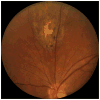

Methods: A selected review was performed on 1390 charts of patients attending the uveitis clinic at the Oregon Health and Science University between 1985 and 2010. Included in the review were all patients with diagnoses commonly associated with retinal vasculitis and all patients who were diagnosed with a systemic vasculitis. Retinal vasculitis was identified by perivascular exudates, intraretinal hemorrhage, or cotton wool spots as seen on clinical examination or by vascular occlusion or leakage as identified by fluorescein angiogram.

Results: Two hundred seven or 14.9% of patients with uveitis had retinal vasculitis as a component of the intraocular inflammation. Thirty-five patients had retinal vasculitis that was primary, ie, not associated with a systemic disease, and the dominant manifestation of the uveitis. Fourteen of the patients with retinal vasculitis had Behcet's disease. Only 11 of the 1390 patients with uveitis had a systemic vasculitis. Of these 11, four had retinal vasculitis including 1 secondary to a cytomegalovirus retinitis. Thus, systemic vasculitis was directly responsible for 1.4% or 3 of 207 cases of retinal vasculitis. Nonvasculitic systemic diseases such as sarcoidosis (n = 13), syndromes confined to the eye such as pars planitis (n = 36), and intraocular infections (n = 29) were far more common causes of retinal vasculitis.